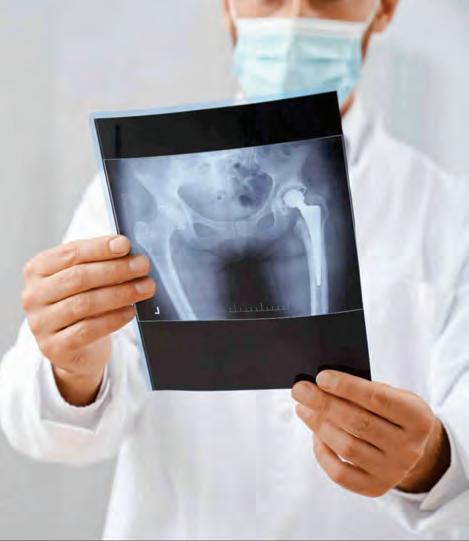

FRACTURA DE CADERA

Las fracturas de cadera son lesiones comunes y graves, para las personas de la tercera edad, actualmente consideramos un gran aumento en la frecuencia que esta se presenta, debido a tres factores: mayor índice de sobrevida, en consecuencia, más osteoporosis, peor estado nutricional y accidentes de mayor energía. Estas fracturas pueden tratarse mediante diferentes técnicasquirúrgicas:

ClavoCentromedular(CCM):

-Menorincisión

-Menorsangrado

- Valido para fracturas que están afuera de la articulación

-Deambulacióninmediata

-Mayorriesgodetromboembolia

-Riesgodedesanclarse

PrótesisdeCadera:

-Sepuederealizarconosincemento

-Usadoenfracturasarticulares

-Riesgodeluxación

-Fracturaspordebajodelaprótesis

-Granniveldesangrado

En resumen, tanto el clavo centromedular como la prótesis de cadera son opciones para el tratamiento de fracturas de cadera. La elección depende de la situaciónclínica,laedaddelpacienteylapreferencia del cirujano. Es fundamental evaluar cada caso individualmente para determinar la mejor opción terapéutica.